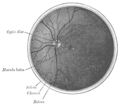

Cross-section of human eye, with choroid labeled at top. | |

Interior of anterior half of bulb of eye. (Choroid labeled at right, second from the bottom.) | |